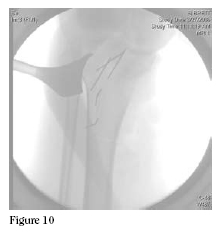

flap. Then, using C-arm control, K-wires were placed outlining

the length and extent of our osteotomy. (Figures 10 and

11) An oscillating saw and osteotomes were used to make the

osteotomy. We had direct visualization of the articular surface

at this point and placed the osteotome just medial to the tibial

spines, preserving the insertion of the cruciates by undercutting

of the tibial spines. The osteotomies were completed, the

specimen was passed off, and curettings were taken for a deep

margin. (Figures 12 and 13)